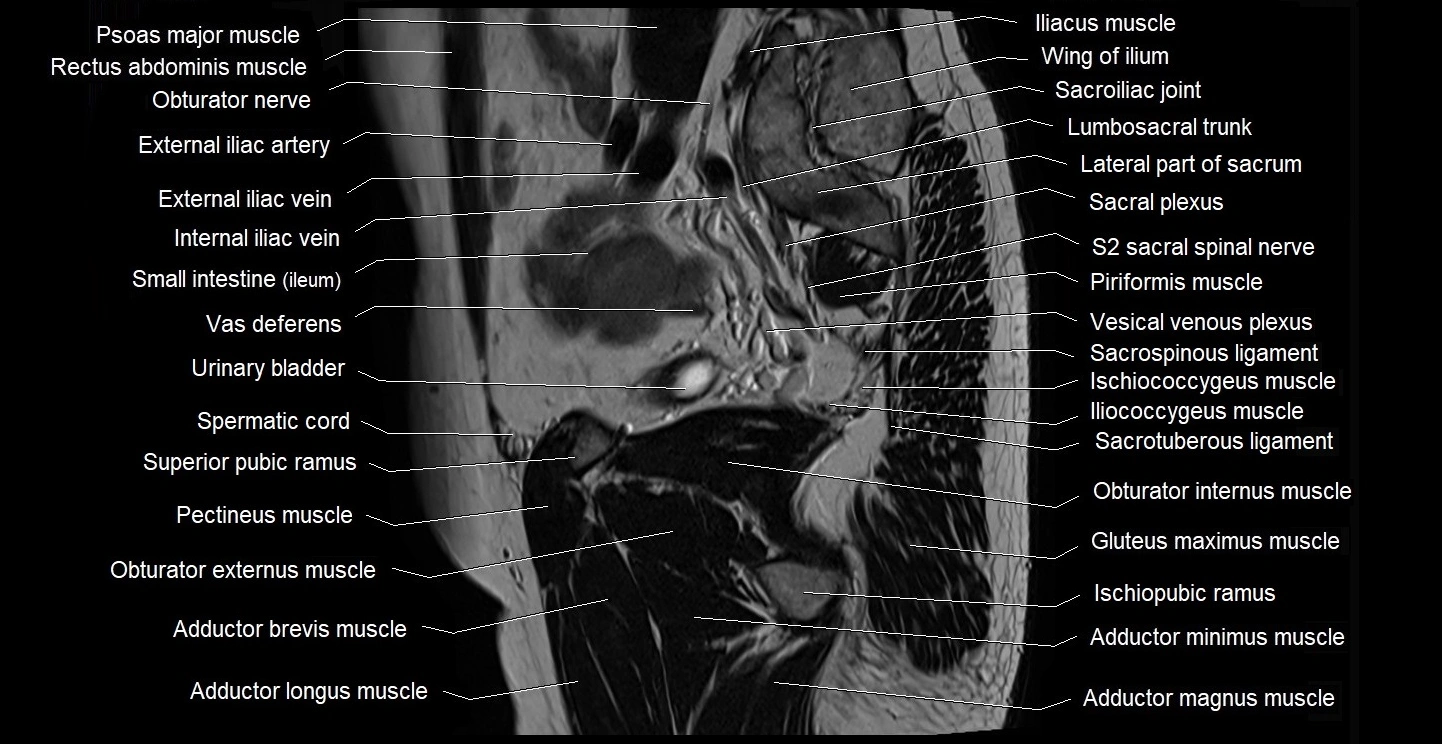

- Lumbosacral trunk

- Obturator nerve

- Pectineus muscle

- Piriformis muscle

- Psoas major muscle

- Sacral plexus

- Sacroiliac joint

- Sacrospinous ligament

- Sacrotuberous ligament

- Sciatic nerve

- Seminal vesicle

- Spermatic cord